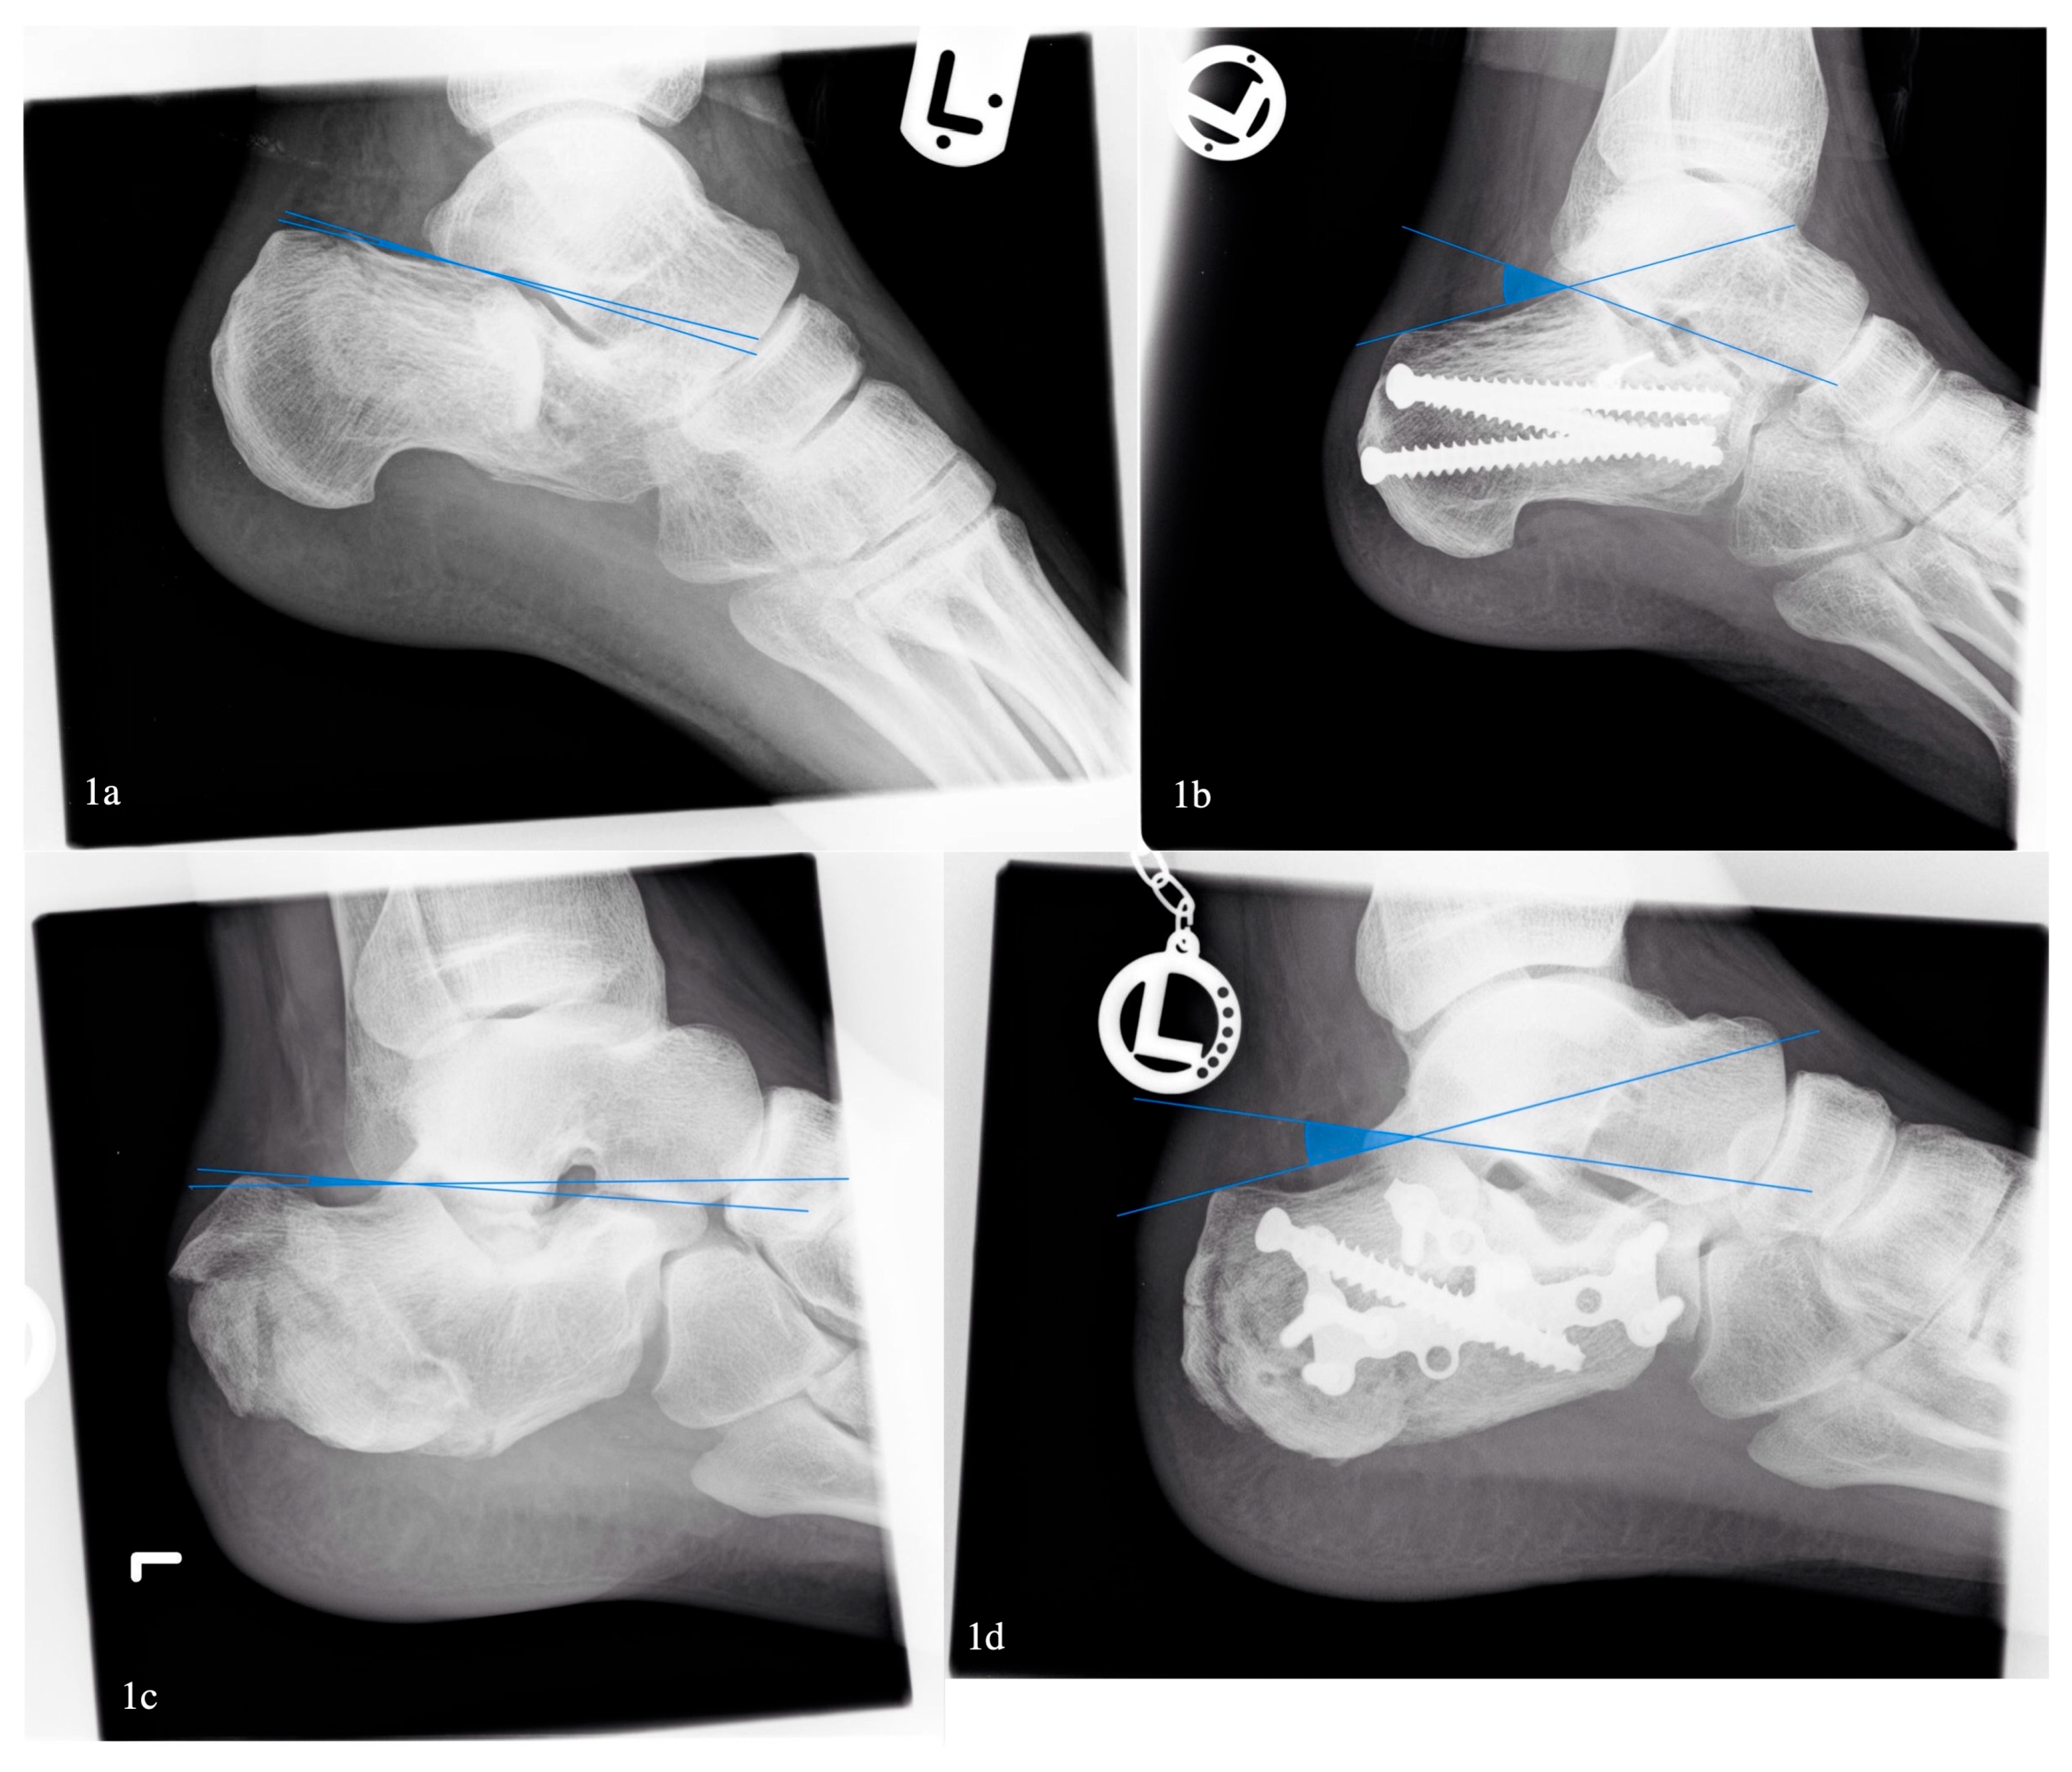

A Böhler angle below 0 degrees was associated with higher overall complication rates (33% vs. 17%, p < 0.05), but no significant difference in wound complications was found (27% vs. 12%, p = 0.55) (Figure 1). After exclusion of open fractures, the association between a low Böhler angle and complications vanished.

Figure 1. Comparison of pre- and postoperative Böhler angle. Pat. 1: (1a) 2° preoperative, (1b) 35° postoperative; Pat. 2: (1c) 5° preoperative, (1d) 23° postoperative.

Our findings that a Böhler’s angle below 0 degrees is associated with a significantly higher overall complication rate are consistent with previous studies identifying a low Böhler’s angle as a predictor of poorer outcomes and higher complication rates in calcaneal fractures [8,9,17]. A severely decreased or negative Böhler’s angle reflects substantial collapse of the posterior facet and disruption of the calcaneal structure, which has been associated with greater soft tissue trauma and mechanical instability [8]. However, after excluding open fractures in our study, the association between Böhler’s angle and overall complications was no longer observed, suggesting that soft tissue injury severity, rather than bony deformity alone, may be the principal driver of complications. This aligns with recent studies emphasizing the critical role of soft tissue condition, particularly in high-energy injuries, on postoperative outcomes. This finding reinforces recent evidence that early assessment of soft tissue status should guide both surgical timing and treatment strategy [22].